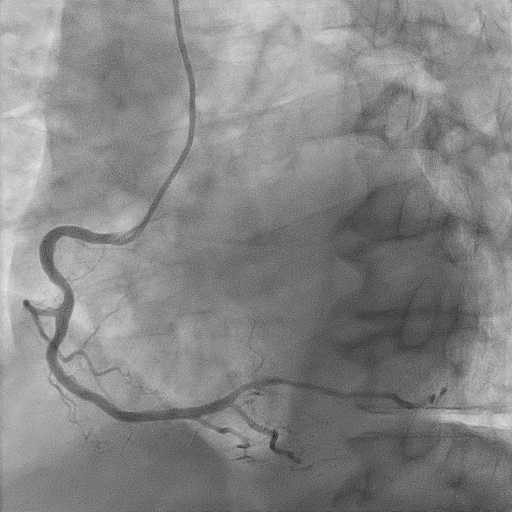

We proceeded with delayed selective PCI to the left anterior descending artery (LAD). The left main coronary artery (LMCA) was engaged with guiding catheter Medtronic Launcher 6FR EBU 3.5. The PTCA guide wire Shun R (SHUNMEI Medical) crossed the lesion with ease. Besides, we wired the diagonal 1 with PT2 (Boston Scientific) to provide side branch protection. The proximal to mid segment of the LAD lesion was pre-dilated with Sapphire NC 24 PTCA balloon 3.0x15mm and inflated to 12 atm. The lesion was stented with Xience Xpedition 3.0x48mm and inflated to 10atm. The stent was post-dilated with NC Trek balloon 3.5x12mm and inflated to 14atm. Noted while retracting the balloon during post-dilatation, the guiding catheter advanced deep into the LMCA several times. Subsequently, patient became progressively hemodynamically unstable. Trial of aspiration with Genoss Extractor but no thrombus was aspirated. Intracoronary Tirofiban bolus was administered. Unfortunately, patient went into cardiorespiratory arrest and intensive resuscitation was commenced. Angiography showed severe flow-limiting type D dissection of the LMCA. We proceeded with rescue stenting of LMCA with Xience Sierra 3.5x38mm with inflation to 12atm. The stent was post-dilated with NC Euphora 4.0x8mm and inflated to 18atm. The final result was TIMI flow 3 but the stent was about 3 to 5 mm proximal to the LMCA ostium. An intra-aortic balloon pump was also inserted and patient required 4 inotropes.